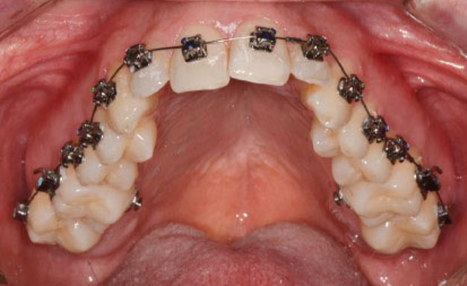

The final 4 months were focused on arch coordination and detailling.

Individually coordinated stainless steel archwires, using the WALA ridge described by Dr. Andrews as the reference

(image: Finishing wires)